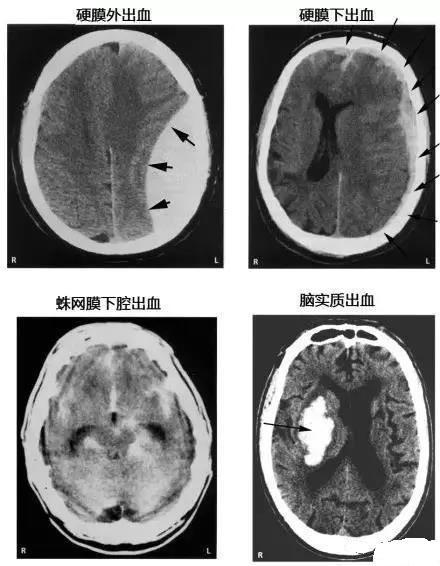

15. 几种类型脑出血的CT表现

点击图片可查看大图详情